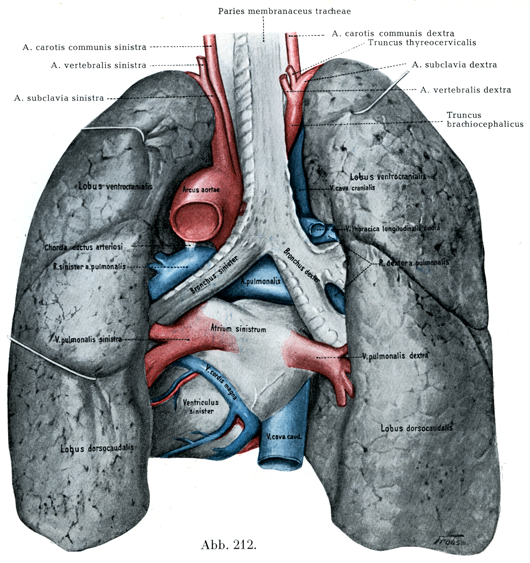

土日祝日は休業日となっております。Rauber-Kopsch解剖学。